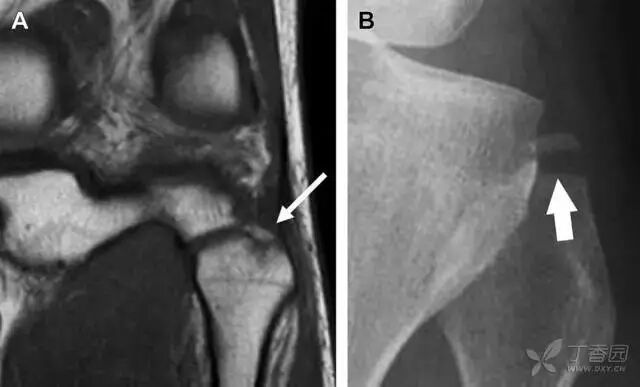

在常规前后位片上,大结节与肱骨头重叠,骨折不易发现,外旋位前后位片有助于诊断。

图 1 大结节骨折。(A)脂肪抑制序列斜冠状位 MRI,显示肱骨大结节线性骨折无移位(箭头)与周围骨水肿;(B)外旋位前后位(AP)片,证实大结节骨折(箭头),典型的骨折愈合过程中的骨吸收表现;(C、D)初诊时内旋位、外旋位前后位片,初诊时漏诊,仔细回顾影像,内旋伞下可见双密度影(椭圆),骨皮质中断(箭头)